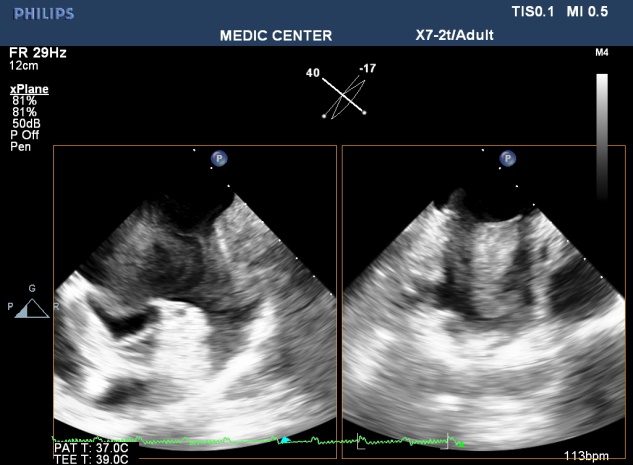

Because patients often presented late in Hospitals, their Wilkins score usually is high (68% with Wilkins score is superior to 8). Especially, LAA thrombus, even small size, furthermore, can be detected more clearly on RT- 3DTEE. Volume and mobility of LAA thrombus appreciated better on 3DTEE.

Detection LA and LAA thrombus by RT-3DTEE is more sensitive than 2DTEE with X-plane mode and 3 D Zoom only are avaible in 3DTEE.

Figure 6. X-plane imaging visualizes LAA thrombus in two orthogonal planes

Figure 9. MS with spontaneous contrast and thrombus in LA& LAA, 2DTEE plane of 60°

Assessment of consequences on the LA and LAA ( study LA volume, LAA thrombi ) using X-plan function and 3D Zoom should be preferred because it is accurate and strongly related to predicting thromboembolic events and detecting thrombi [15]. Thrombi in LA and LAA were recorded on 24 patients with AF and 4 patient with sinus rhythm in our study results.